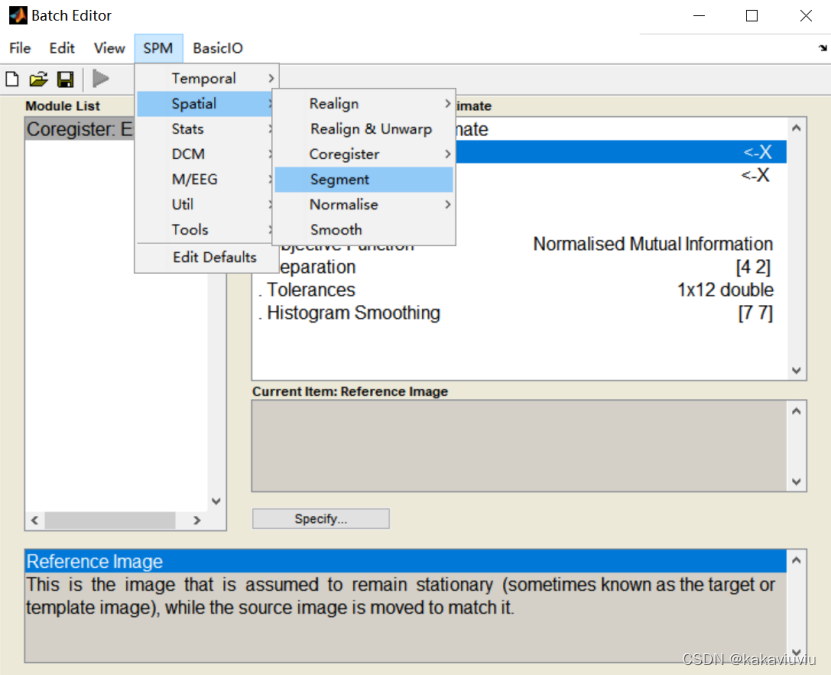

然后点segment(也可以先选,之后来设置这些参数)